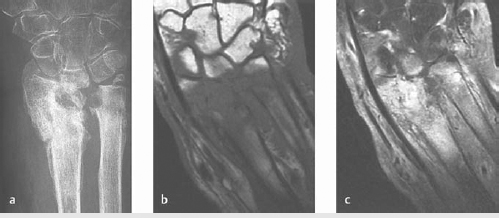

Radiographs obtained first can show lucencies/sclerosis and periosteal reaction.

MRI with contrast best test to assess for extent of infection and assist in surgical planning (► Fig. 13.2).